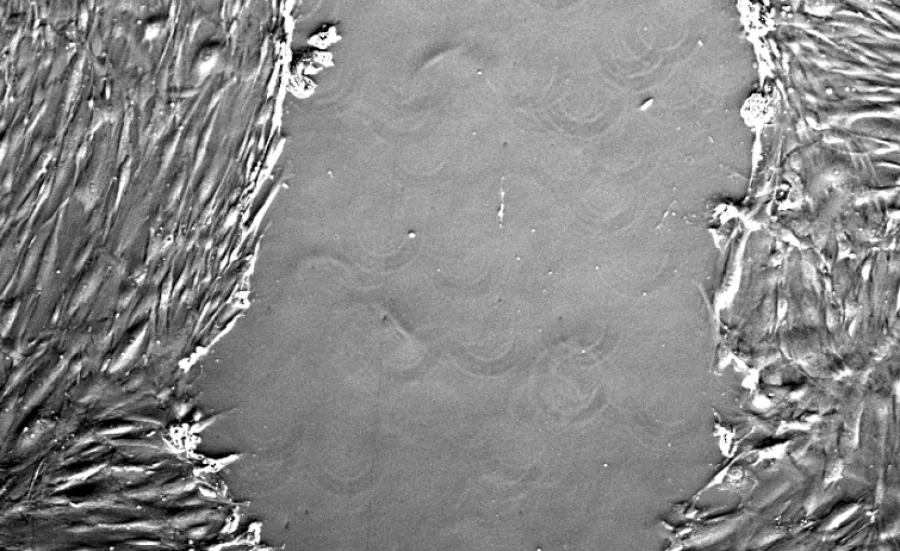

A fully automated, inverted microscope system with brightfield, phase contrast and fluorescence imaging capabilities and long working distance objectives.

The microscope system is housed within an incubator chamber to allow long term observation and recording of cells in conventional microplates, flasks and petri dishes.

• bright field and phase contrast imaging